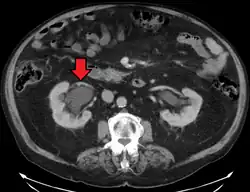

CT scan of bilateral hydronephrosis due to a bladder cancer -